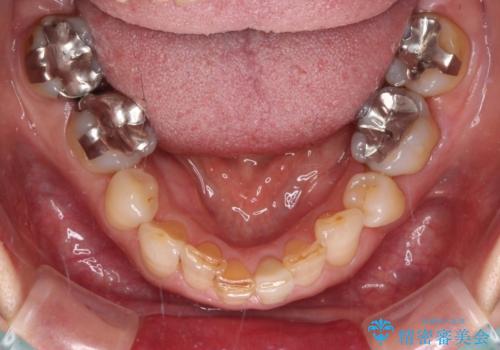

- 下顎前歯が痛んで近医を受診したところ、下顎前歯2本を抜歯してインプラント治療が必要と診断されたとのことで来院された患者様です。

診査の結果、下顎左側中切歯の神経が失活していることが痛みの原因であり、根管治療を行う必要があると診断されました。

根管治療を行った後にオールセラミッククラウンにて補綴することとしました。

隣在歯にも根尖部の炎症が及んでいるように見えましたが、術前診査では神経が失活している様子がなかったため、まずは原因歯から処置を行うこととしました。

初回の根管治療後には痛みが速やかに改善し、6か月後のレントゲン写真では根尖の病変が消失していることが確認できました。